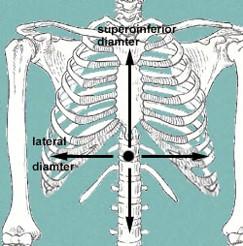

what 3 things to assess during a PE with patterns of ventilation?

what 2 things should we look for in inspiration?

Physical exam ...assess rate, symmetry, quality of movement, etc…

Inspiration ...increase in AP and lateral diameter due to “bucket

handle” motion of ribs

increase superior to inferior length

look at pictures to help visualize